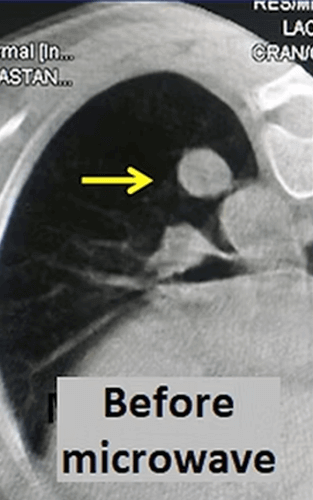

In our patient with a 3 cm tumor (*) in his left lung, microwave ablation was performed using two antennas. The PET-CT taken at 4 months after the procedure shows that the tumor has shrunk markedly and its activity disappeared almost completely.

Another ablation method that has become popular in lung cancer in recent years is microwave. Microwave ablation provides a faster and stronger ablation than radiofrequency. However, unlike liver, there is not enough information about the efficiency and complication rates in the lung. In microwave ablation, the microwave antenna is placed in the center of the tumor with CT guidance and the tumor is ablated for 3-10 minutes under general anesthesia or deep sedation. For microwave, tumors that are located in the middle of the lung and less than 3cm in diameter are more suitable.

In our female patient who had metastases of salivary gland cancer in her lung, microwave ablation was performed to the largest mass with a diameter of 2 cm. One year later, the follow-up CT reveals only a small fibrotic remnant (arrow).